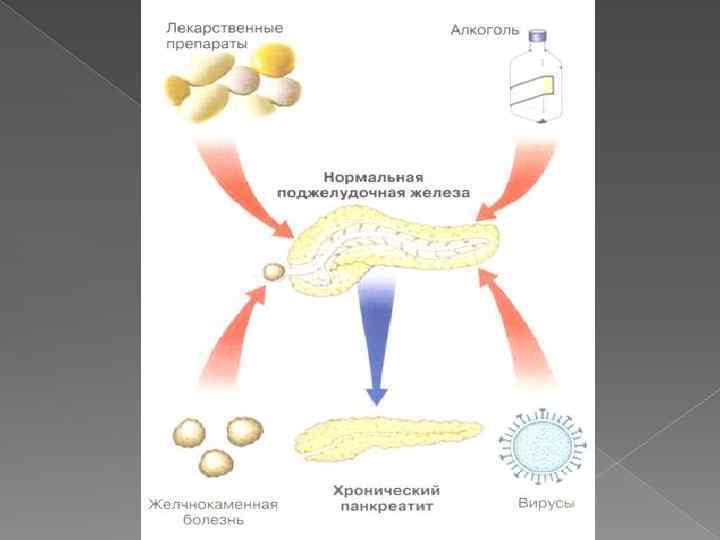

Причины панкреатита: - интоксикация алкоголем - заболевания желчных путей, желчного пузыря - заболевания двенадцатиперстной кишки (дуоденит, гастродуоденит, язва) -избыточная пищевая нагрузка - травмы - прием лекарств - иммуносупрессанты, антибиотики, сульфаниламиды, непрямые антикоагулянты, индометацин, бруфен, парацетамол, гормоны, эстрогены; - инфекции (в том числе вызванные вирусами гепатита В, С);

Причины панкреатита: - интоксикация алкоголем - заболевания желчных путей, желчного пузыря - заболевания двенадцатиперстной кишки (дуоденит, гастродуоденит, язва) -избыточная пищевая нагрузка - травмы - прием лекарств - иммуносупрессанты, антибиотики, сульфаниламиды, непрямые антикоагулянты, индометацин, бруфен, парацетамол, гормоны, эстрогены; - инфекции (в том числе вызванные вирусами гепатита В, С);

Существует две основные формы острого панкреатита: - панкреатит, вызванный закупоркой протоков железы желчными камнями - алкогольный панкреатит, возникающий приеме алкогольных напитков

Существует две основные формы острого панкреатита: - панкреатит, вызванный закупоркой протоков железы желчными камнями - алкогольный панкреатит, возникающий приеме алкогольных напитков